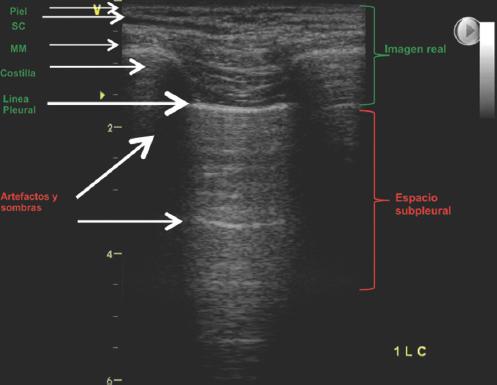

La ecografía actúa como un densitómetro pulmonar, permitiendo distinguir entre tres patrones fundamentales en función de la proporción entre aire y fluido: patrón A de aireación, patrón B de intersticial y patrón C de consolidación16 (Fig. 1).

Figura 1 Ventana acústica en ultrasonido pulmonar normal. Nótese el campo pulmonar que se genera entre las dos sombras acústicas generadas por las costillas y la línea pleural hiperecogénica correspondiente a la pleura parietal, que con los movimientos respiratorios dará el deslizamiento (slidding) y los artefactos que se generan inferior a ella. MM: masa muscular; SC: tejido subcutáneo.